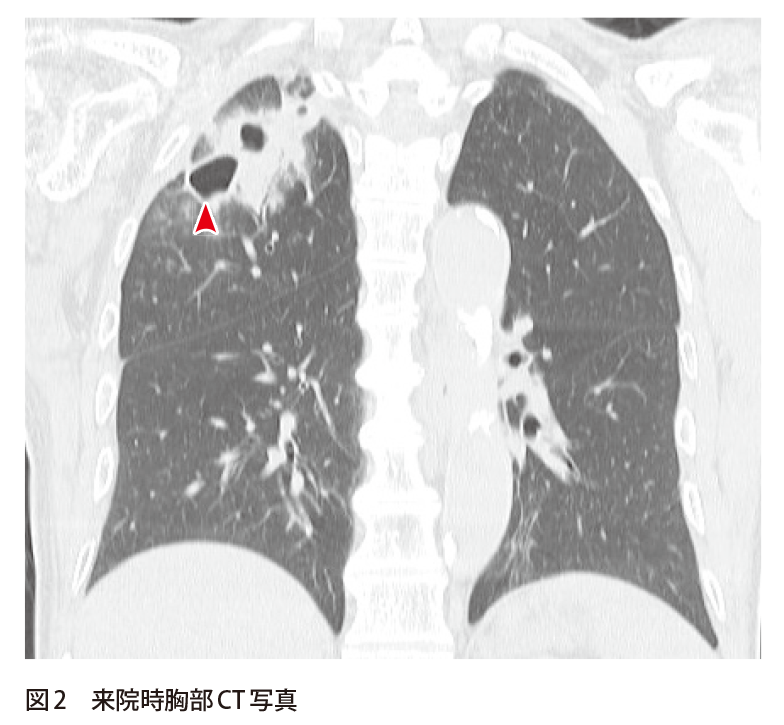

解答 解説 微熱 全身倦怠感を主訴として来院した70歳代男性 実践 画像診断q A 羊土社 レジデントノート 羊土社